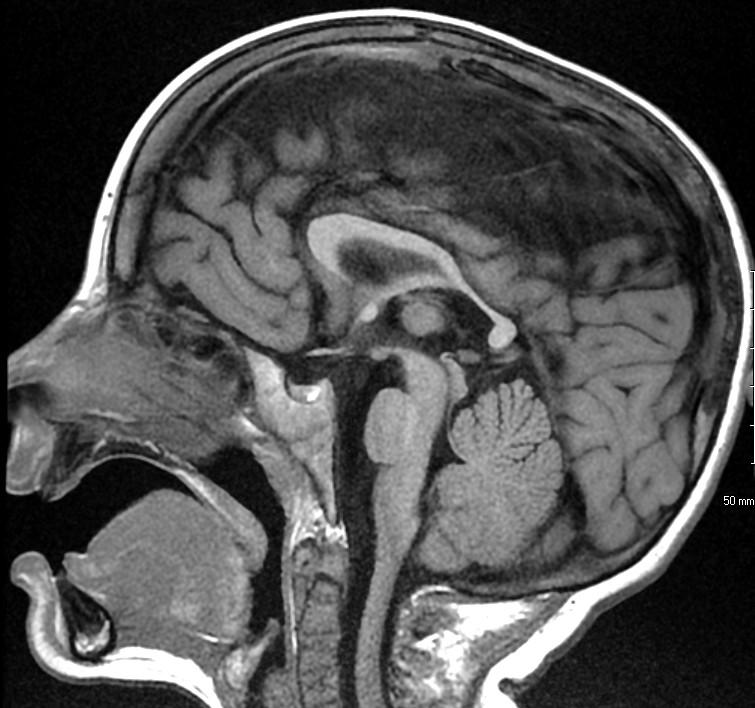

White arrows: Small pons remnant with nonformation of the midportion of the brainstem

Clinical: cranial neuropathies

Associated with small cerebellum

Abnormal vertebrobasilar vasculature

Etiology?

very early vascular insult?

No gliosis to suggest hypoxia or ischemia

In animals: seen with hox gene deletions leading to lack of single rhombomere development, so brainstem “short” but typically not fully disconnected